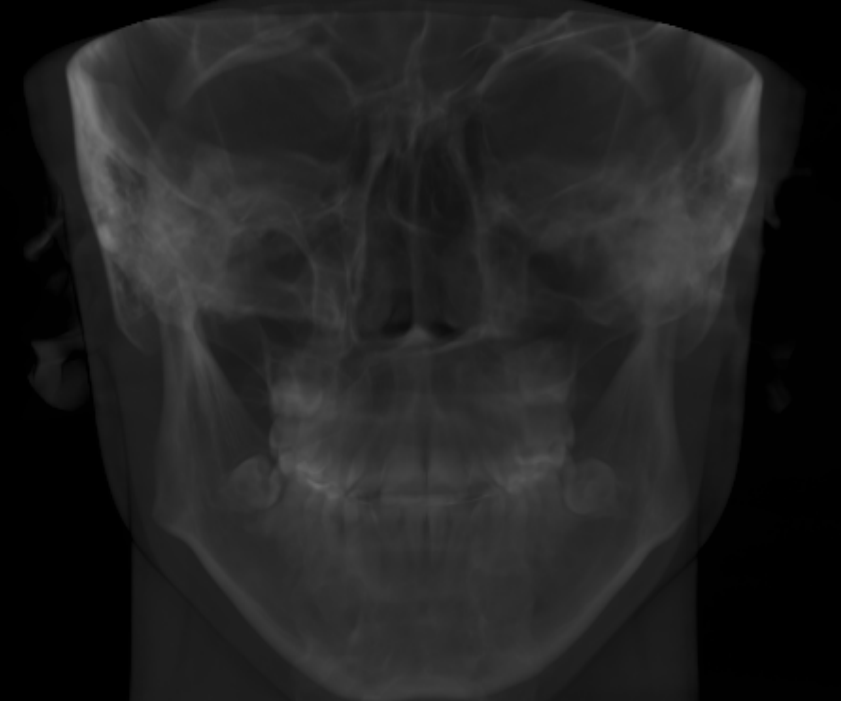

Double Jaw Surgery + Genioplasty

At least 4* of counter clockwise rotation on both jaws.

5mm+ advancement on both maxilla and mandible

7mm+ genioplasty

Double Jaw Surgery + Genioplasty

At least 4* of counter clockwise rotation on both jaws.

5mm+ advancement on both maxilla and mandible

7mm+ genioplasty